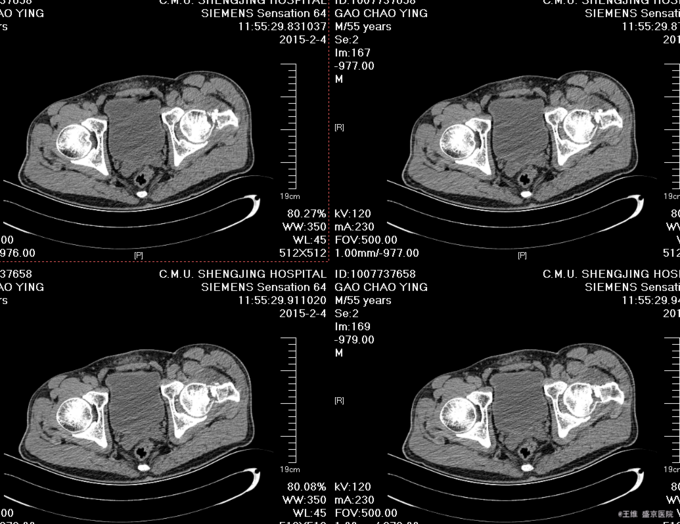

患者自述于2015-12-3日15时在工厂干活时不慎由梯子上摔落(高约3米),致左髋部疼痛、活动受限,不能站立行走,急送至当地医院行骨盆DR示:左股骨颈骨折。现患者为求进一步诊治来我院,急诊以“左股骨颈骨折”为诊断收入我科。患者自受伤以来一般状态可,无发热,无头晕、呕吐,无胸闷、心悸呼吸困难,无腹痛、腹泻,饮食可,睡眠可,二便正常。

患者入院后完善相关检查,查无明显手术禁忌症后,CSEA下行左股骨颈骨折闭合复位空心钉内固定术,术后患者抗炎等对症治疗,患者第二天退院。嘱患者卧床休息3个月后,复查。